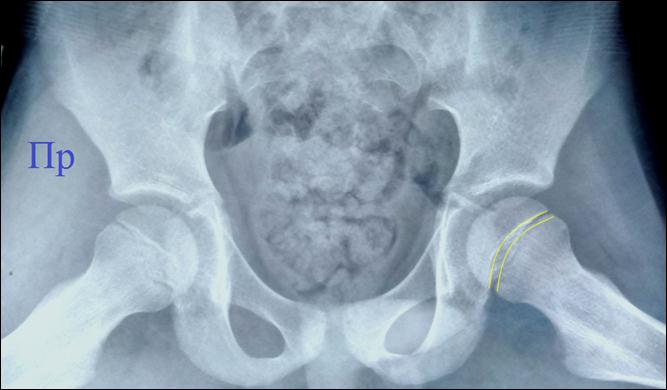

Костный

мостик, прошивающий зону роста головки бедра у мальчика 12 лет с юношеским

эпифизеолизом головки бедра слева.

Фронтальный скан РК – томографии.

Давность заболевания 6 месяцев, за помощью не обращались. На момент

осмотра: небольшая хромота, жидкость в полости левого тазобедренного сустава,

боли при ходьбе.